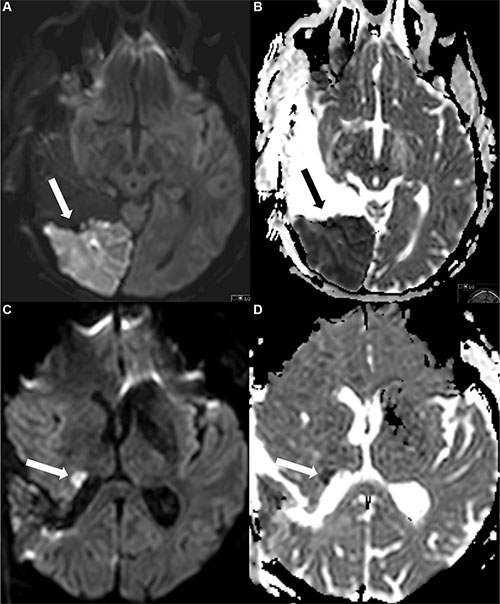

Image analysis was performed by a neurosurgeon (9 years of experience) and a neuroradiologist (6 years of experience) in consensus, blinded to neurological outcome and overall survival. Areas of ischemic lesions were defined by a focal hyperintensity on diffusion-weighted images and a corresponding hypointensity on ADC maps, excluding methaemoglobin and postoperative changes as it was described before [10, 38] (Figure 4).

Figure 4: Examples of postoperative ischemic changes. The first row (Figure A and B) shows a large area with restricted diffusion (A) and corresponding hypointensity in the ADC map (B), the second row a smaller area with restricted diffusion (DWI) (C) and ADC (D) map.